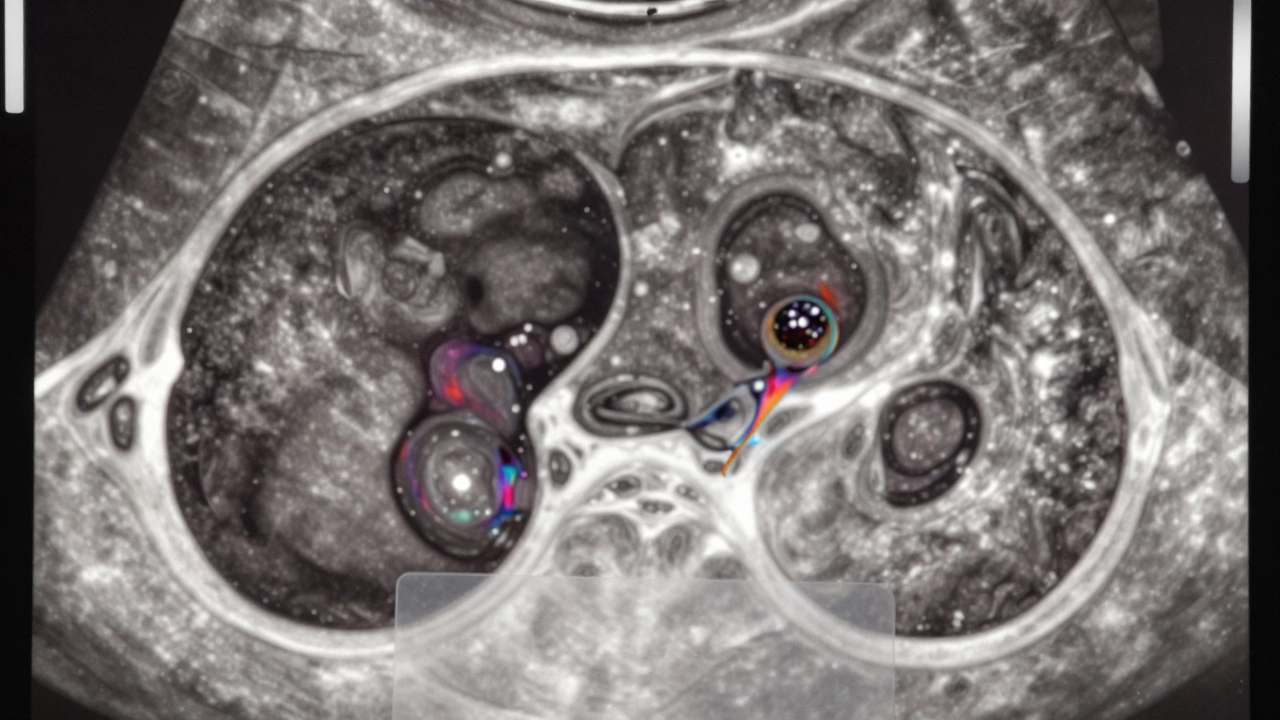

Вот где начинается сложность. УЗИ может показать кисту, которая выглядит не так, как «идеальная». Например:

• Внутри есть перегородки - тонкие или толстые.

• Стенки кисты неровные, утолщенные.

• Есть включения - плотные участки внутри жидкости.

• Кровоток в стенке или перегородке - это тревожный признак.

• Размер больше 5 см или растет за несколько месяцев.

Такие кисты называют сложными или атипичными. И здесь УЗИ уже не может сказать: «Это эпидермоидная киста» или «это серозная киста яичника». Оно говорит: «Это не обычная киста. Нужно смотреть глубже».

Сложная киста молочной железы на УЗИ с перегородками и кровотоком в стенке